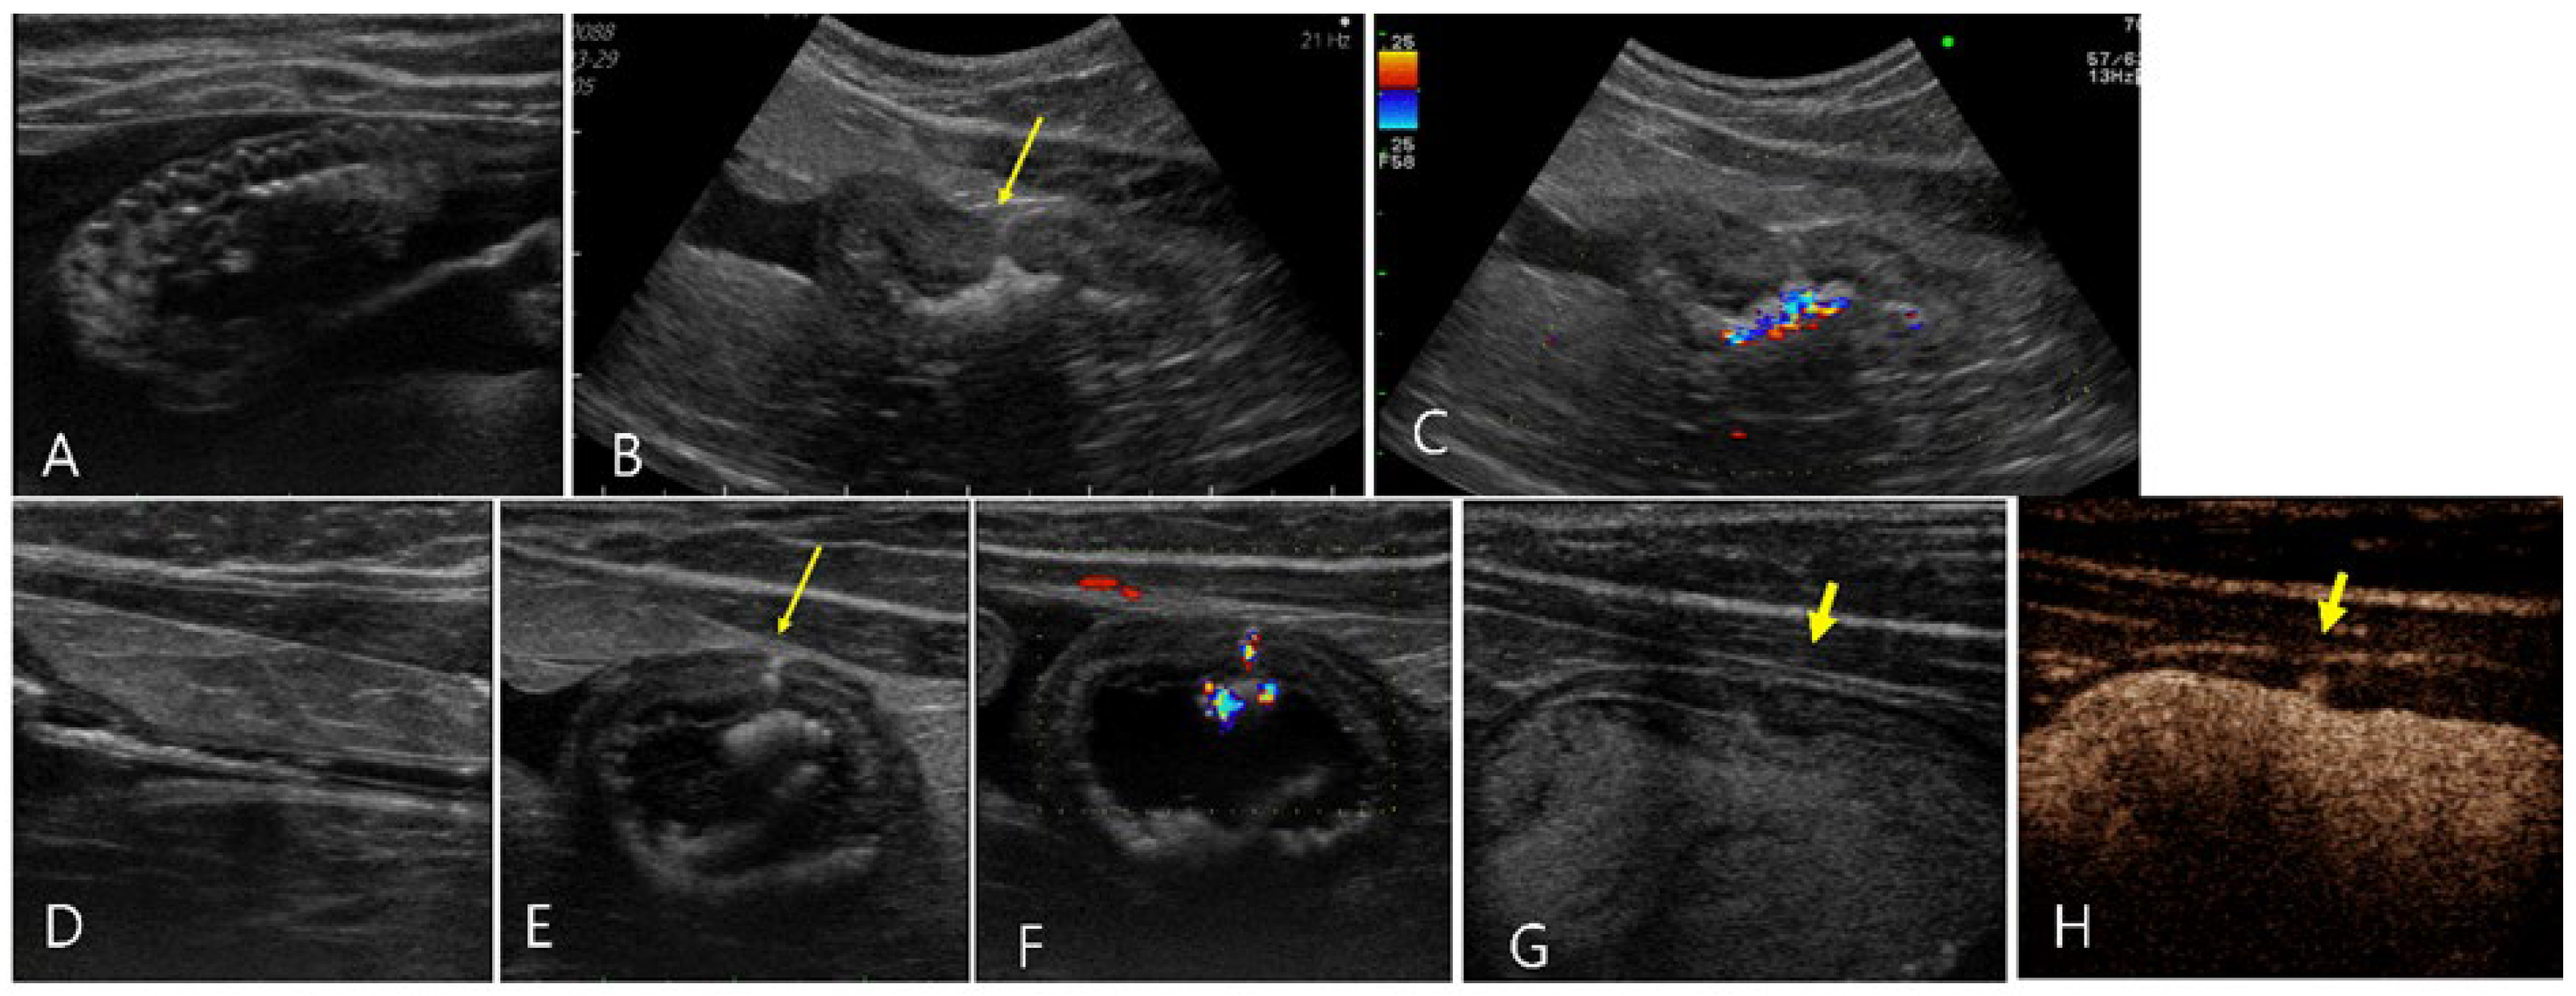

2.4. Case 4

2.5. Case 5

2.6. Case 6